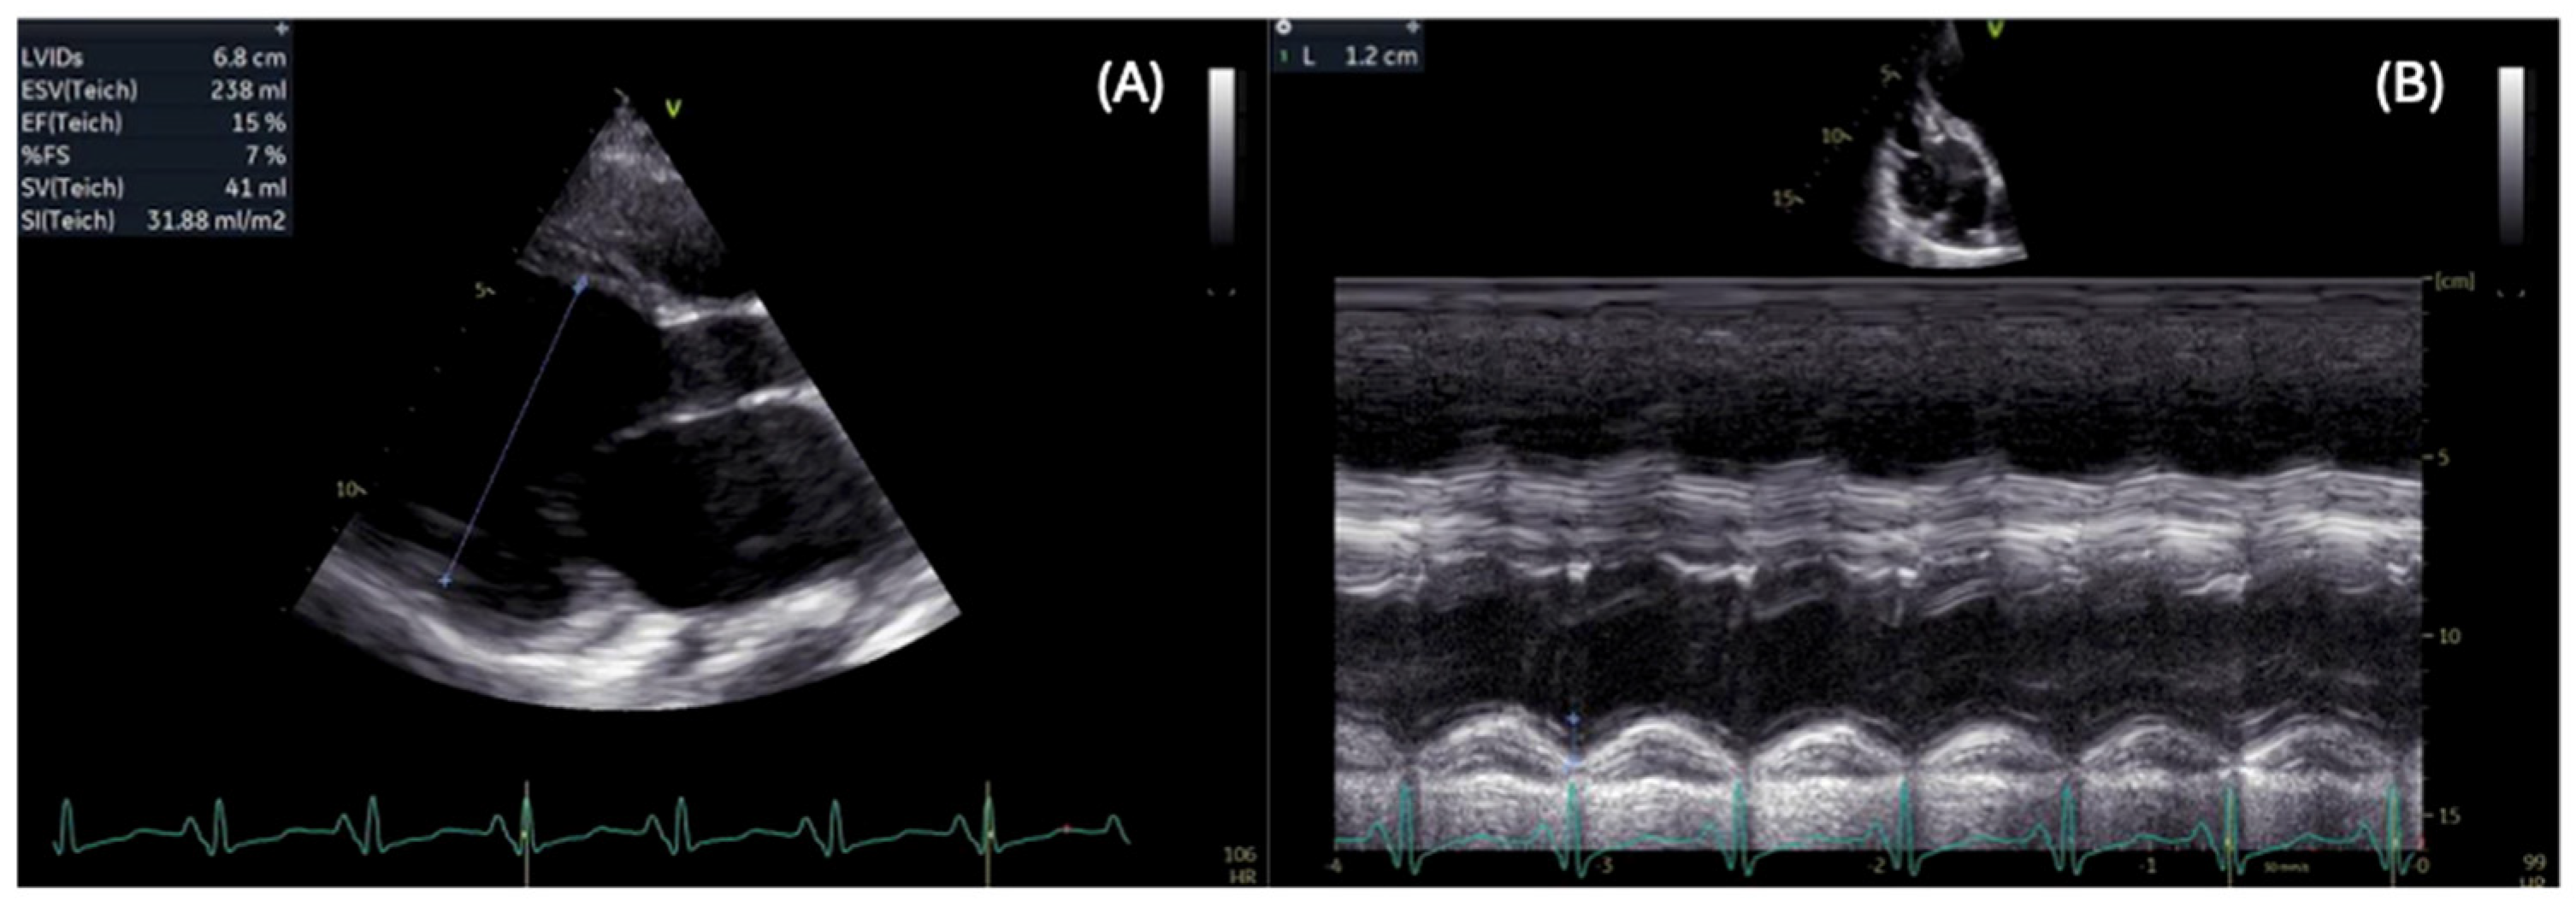

- Piperata, A.; Bottio, T.; Toscano, G.; Avesani, M.; Vianello, A.; Gerosa, G. Is heart transplantation a real option in patients with Duchenne syndrome? Inferences from a case report. ESC Heart Fail. 2020, 7, 3198–3202. [Google Scholar] [CrossRef] [PubMed]